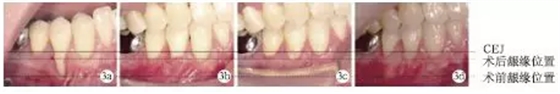

術(shù)前#44頰側(cè)牙齦退縮達9mm;術(shù)后兩周、術(shù)后兩個月及術(shù)后1年,頰側(cè)齦退縮減少為2mm,根面覆蓋率為:77.8%,未見進行性牙齦退縮(圖3)。

圖3 術(shù)前及術(shù)后根面牙齦覆蓋情況對比

術(shù)前#44頰側(cè)角化齦寬度極少,小于1mm;術(shù)后2個月及術(shù)后1年,可見角化齦寬度增加為2mm,且角化齦厚度也明顯增加,見圖4。

圖4 術(shù)前及術(shù)后頰側(cè)角化齦寬度對比